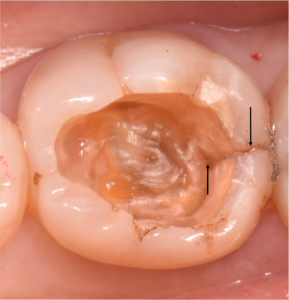

今回歯の上部は健全な部分がたくさん残っているので、上から直径3ミリほどの小さな穴を開けそこから、根の内部の吸収部を除去しようと試みました。

すると吸収部にはただ単に歯が溶けているのではなく、肉芽という歯茎の一部が入り込んでしまっているので、穴を開けた瞬間に血が噴き出してきて、血まみれで中を見るのが困難な状態でした。